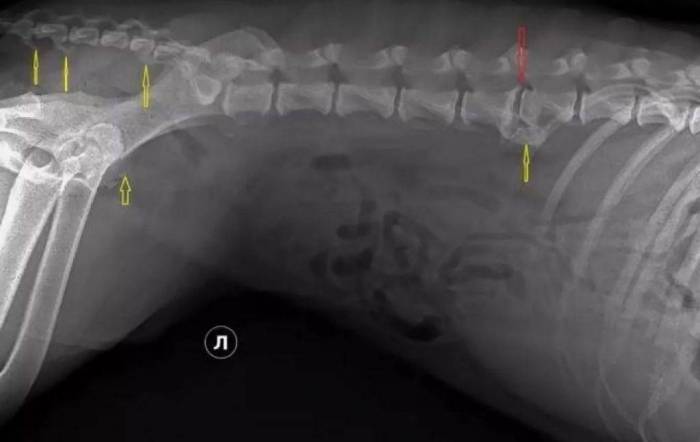

Диагностика начинается с рентгенографического исследования позвоночника. На снимке сам межпозвоночный диск не отображается, однако изменения в костных структурах позвонков, соседствующих с повреждённым диском, будут заметны. Эти изменения становятся видимыми через 2–6 недель после появления первых клинических симптомов. Поэтому при раннем обращении ветеринары обычно делают несколько рентгеновских снимков с интервалом в несколько недель. Основным признаком, который может вызвать подозрение на дискоспондилит, является боль в спине у собаки, которая не устраняется с помощью симптоматического лечения.

- Рентгеноскопия позвоночного столба. Выявляет место поражения и степень. Максимально достоверная картина проявляется при использовании контрастного вещества.

Рентгенография может предоставить полезную информацию для выявления данной патологии, однако она не позволяет точно определить локализацию выпавшего содержимого грыжи.

При рентгенографическом исследовании заболевания межпозвонковых дисков по типу Хансен 1 можно наблюдать сужение межпозвонкового пространства, а также межпозвонковых отверстий и пространства между суставными отростками. В редких случаях, если ядро выпавшего диска обызвествилось, его можно увидеть в позвоночном канале. При заболеваниях межпозвонковых дисков по типу Хансен 2 рентгенограмма демонстрирует иную картину. При хронических проблемах, помимо сужения межпозвонкового пространства и отверстий, часто наблюдаются склероз суставных пластинок позвонков, образование остеофитов, спондилез и другие изменения. Особенно выражены эти признаки при люмбо-сакральном стенозе, известном как «синдром конского хвоста».